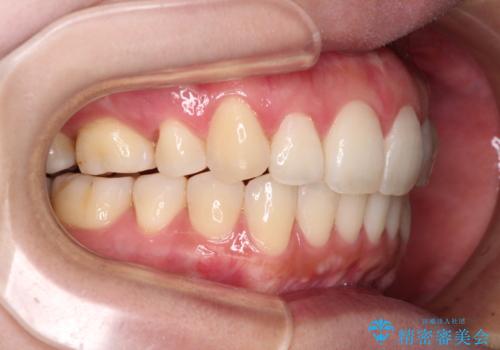

再矯正で突出した口元を引っ込める 抜歯矯正の後戻り

- 抜歯矯正の後戻りで前歯が突出してきていることを気にして来院された患者様です。

口元の突出感を改善するにあたり、抜歯矯正は行うことができないため、奥歯の後方移動とIPR(歯と歯の間を削る)により達成することとしました。

再度後戻りしたときに対応しやすいよう、インビザラインにて矯正治療を行うこととしました。

しっかりと装着時間を守り、ゴムかけにも協力していただいたので、口元を引っ込めることができました。